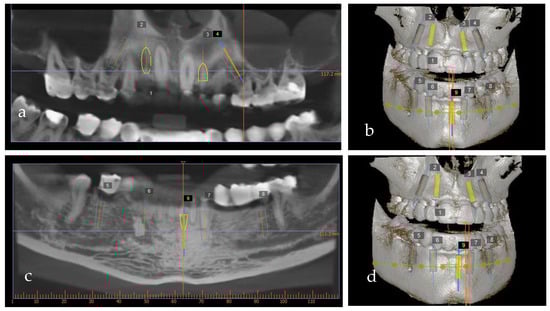

Figure 8.

Implant planning software using cone-beam computerized tomography: (a,b) maxilla and (c,d) mandible.

Using digital planning, the placement of nine implants, four on the maxilla and five on the mandible, was established (Figure 8a–d) based on the position of the provisional restorations. The implants were planned to be placed in the optimal prosthodontic position; tooth size, bone quality and volume, and the location of the mandibular nerve and sinus were also taken into consideration.

The wax-up also served as a prosthetic guide for the implant position. To precisely plan the implants’ placement from a prosthetic point of view, a CBCT (PaxFlex 3D, Vatech, Hwaseong-si, Republic of Korea) was performed and an initial digital planning software analysis was conducted with Easy3DPlus version 1.2 (Vatech, Hwaseong-si, Republic of Korea) (Figure 8a–d). Based on the previsualized implant placement, surgical guides were designed (Figure 9a,b), to achieve exact implant placement. The guides were designed in the Blue Sky Plan® software version 4.9.4 (Libertyville, IL, USA) and the surgical templates were fabricated using Dental SG resin (Formlabs, Somerville, MA,USA).